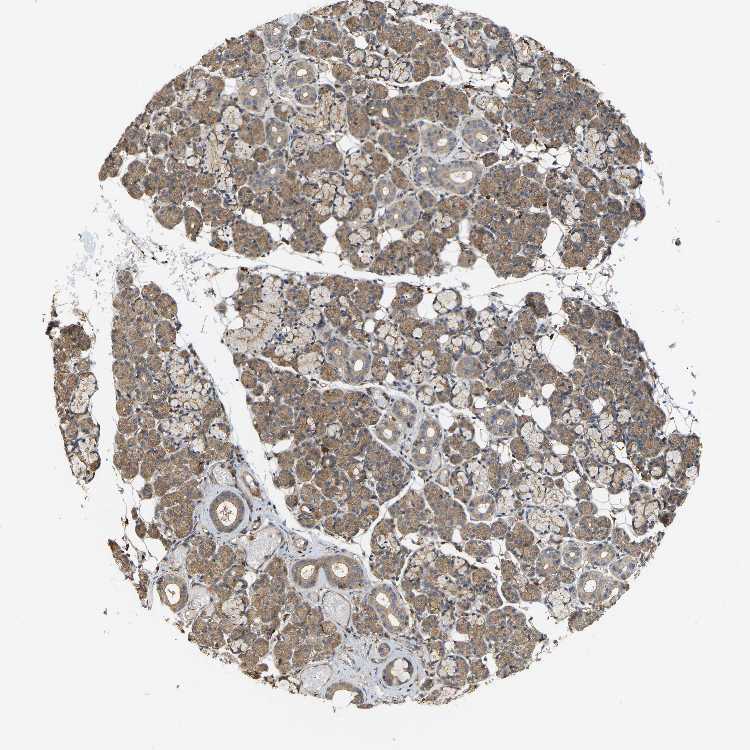

SALIVARY GLAND - Antibody stainingi

Antibody staining in the annotated cell types in the current human tissue is reported as not detected, low, medium, or high, based on conventional immunohistochemistry profiling in selected tissues. This score is based on the combination of the staining intensity and fraction of stained cells.

Each image is clickable and will lead to virtual microscopy that enables deeper exploration of all samples and also displays staining intensity scores, fraction scores and subcellular localization as well as patient and tissue information for each sample.

Antibody HPA019053Antibody HPA019061

Glandular cells MediumNot detected